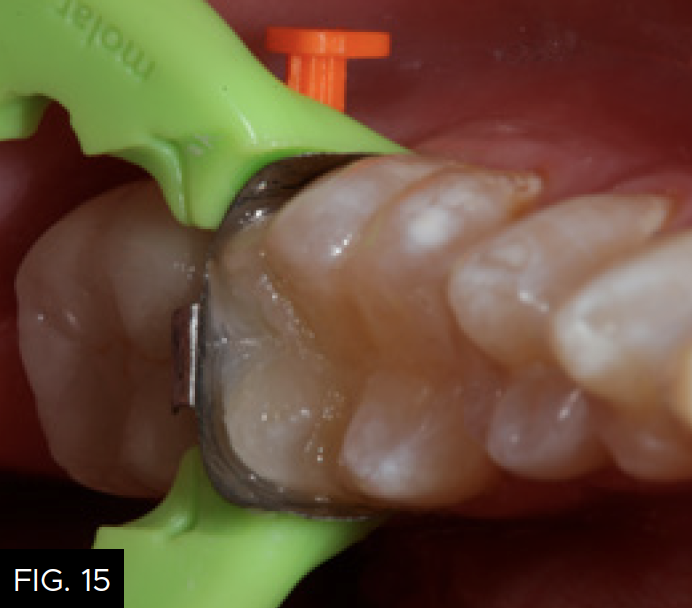

After a five-second etch of the restorative margins with 37% phosphoric acid, a surface sealant (Seal-N-Shine, Pulpdent) is placed with a microbrush, air thinned, and light-cured for 20 seconds. Surface sealants help to seal any microscopic marginal imperfections that may remain after the finishing and polishing process. The same restorative steps are performed for tooth number 19 (36). (FIG. 14 and 15)

A view down the central groove of tooth number 19 (36) is shown after placement of the composite material in the proximal box portion of the cavity preparation. Note that the marginal ridge has a definite facial and lingual component separated by a secondary groove that emanates from the distal pit of the tooth.